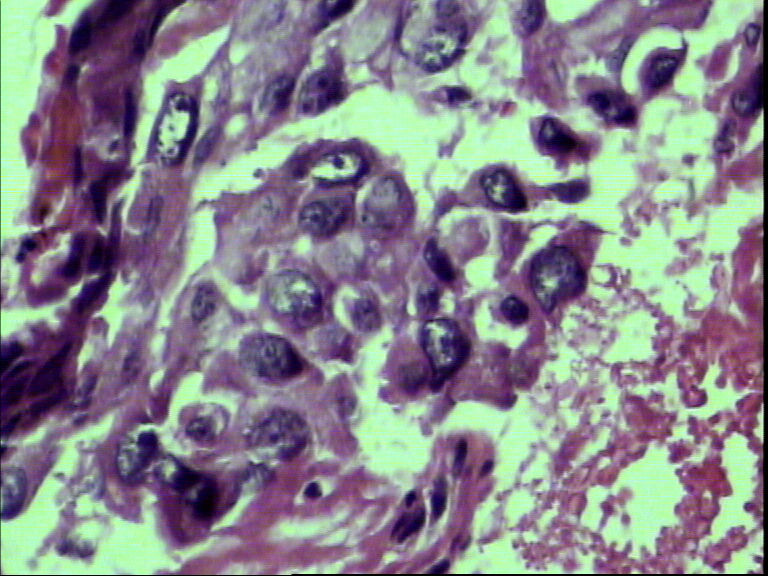

支气管活检,女性,65岁

鳞癌?腺癌?

鳞状细胞癌

组织太少,考虑鳞癌(建议再检)。

就本例而言基本肯定是鳞状细胞癌,退一步讲是腺癌的话,也不需再次活检了,排除小细胞癌了,不影响治疗方案了,只要其他情况还好的话,手术治疗是首选了。

图片质量太差 需排除腺鳞癌